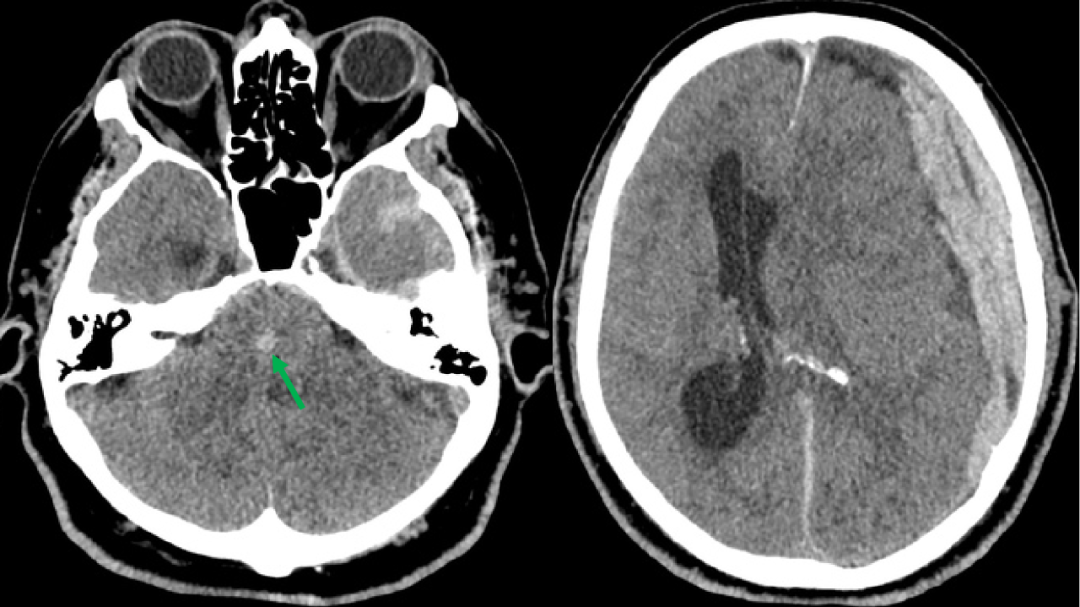

男,54 岁,头部外伤入院,2022-2-12 显示左侧额颞顶部硬膜下血肿,继发大脑镰下疝。2022-2-13 去骨瓣清除硬膜下血肿发现中脑新发出血(绿箭头)。

Duret 出血,位于中脑近中线部位,左侧额颞顶部硬膜下血肿及大脑镰下疝、脑挫裂伤